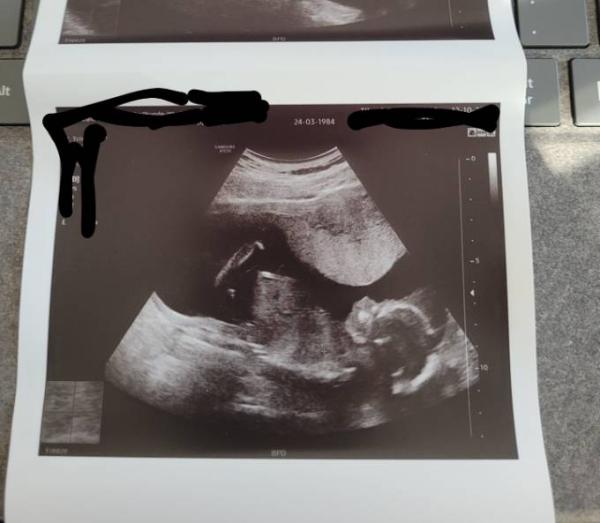

Durfte heute wieder meine kleine Maus sehen. Sie liegt in Querlage. Sie ist schon 21cm groß und 300g schwer. Jetzt bin ich wieder mal ein paar Tage erleichtert und glücklich. War heute noch jemand beim FA?

Mr. Twister ist knappe 18 cm groß und ca 230 g schwer...er ist auch so zuckersüß wie deine Maus